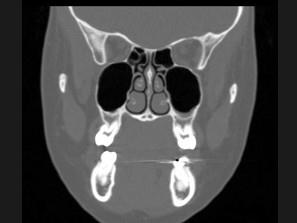

问题 25岁女性,车祸伤及面部,X线及CT检查如图所示,下列哪些描述或诊断正确 ( )

选项 A、考虑为左侧眶底骨折 B、左侧上颌窦积液 C、CT发现左侧眶底骨质断裂 D、左侧上颌窦内见气-液面 E、X线示左侧眶底较正常变低

答案 ABCDE